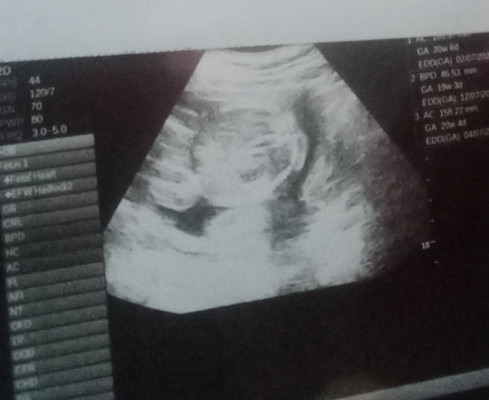

แม่ๆคะ รูปนี้คือตรงหว่างขาน้องหรืออะไรหรอคะ

ไม่น่าจะใช่หว่างขานะคะ